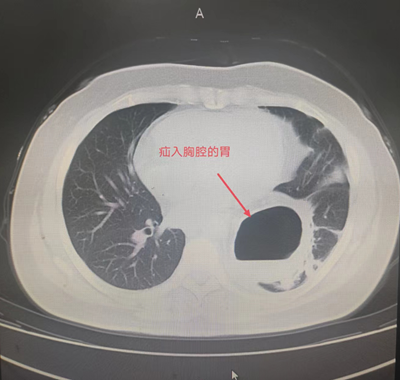

患者辛某,今年85岁,1年前患者因反酸、进食后反复呕吐于外院就诊。胸腹部CT检查提示:膈疝。胃十二指肠镜检查提示:食管外压性改变,膈疝,食管裂孔疝。患者长期营养不良,无法经口进食,只能通过鼻饲-空肠营养管置入进行营养,近日因营养管再次出现导管堵塞,随后被家人紧急送往我院住院治疗。住院后进一步检查诊断食管裂孔疝、肺部感染,既往患有脐疝、胸椎手术史,合并心律失常、低氧血症、代谢性酸中毒、肺大疱、心脏瓣膜疾病、左侧颈动脉斑块形成、腔隙性脑梗塞等老年病史。

由于患者年事已高,病情复杂,手术难度极高。普外科主任田德福充分考虑到患者年龄、病情实际,先组织科室任斌、尹超、杨洲明、何慢等专家进行危重症患者治疗方案讨论。随后联系医务科组织全院多学科MDT讨论,根据全院MDT多科室会诊结果制定了周密的手术计划,并针对高龄患者可能出现的并发症做好各类突发应急准备。在麻醉手术部、手术室的全力配合下,普外科专家团队在全麻腹腔镜下成功为老人实施了食管裂孔疝、膈疝、脐疝三疝同时手术,术中探及食管裂孔疝,直径约4cm,其旁左侧直径约7cm大小膈疝,食管裂孔疝内容物为小网膜组织,膈疝内容物为胃底、胃体大部及大网膜组织。脐疝直径约3cm大小。腹腔镜下进行食管裂孔疝、膈疝无张力修补及脐疝修补术。手术顺利,术中患者生命体征基本稳定。术后在全科医护人员的治疗和精心护理下,逐渐进行经口进流食、半流食。床上活动、渐下床活动。复查各项指标渐正常。胃肠功能恢复正常,于6月14日痊愈出院,近日回访患者一般情况良好。